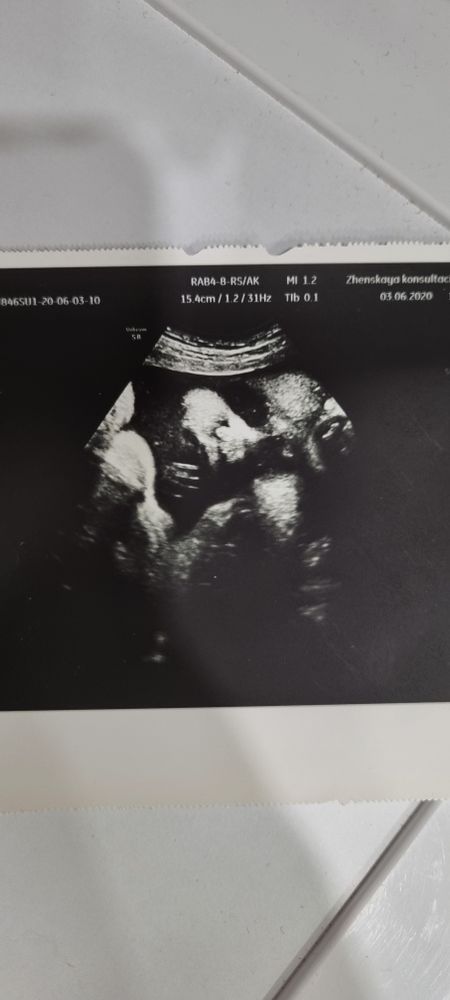

4д узи

УЗИ, КТГ, доплерДевочки, всем привет) дайте совет, сейчас у меня 24 недели. Записалась на 27 число на 4д УЗИ. Хочу сделать для себя и хочу эту милую фотку) кто делал? Есть ли смысл вообще переплачивать и что вообще могут увидеть на этом УЗИ? И кто делал на таком сроке, пришлите, пожалуйста, снимки, если не сложно))

"Цветная"- 15.3 с сыном в 2022г

36, 20.5 и 26.0- на оборудовании ниже классом с дочкой в 2020г

делала 2 скрининг 4д, там качество конечно не то чтобы вау, я особо милого не увидела ничего, но просто видео на диске с узи пересматривала. врач почти 10 минут пытался поймать хороший кадр,тк ребенок закрывал руками лицо. через 2 недели наверное пойду на 3 скрин тоже 4д, не из за фотки))

В 27 недель сделали классные фотки и видео. К сожалению, флешки нет с собой, чтобы прикрепить к сообщению